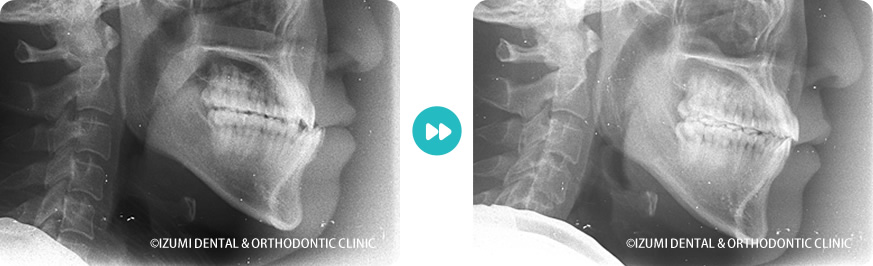

外科(骨切り)処置を回避できた症例01

| 治療内容・装置 | 数件の歯科医院で外科矯正の適応と言われた噛み合わせの方の症例です。 インビザラインでは受け口の症例は少ないですが、当院ではインビザラインの欠点を補うマルチループという治療方法を行っているので、歯を抜くことなくインビザライン+マルチループで治すことができました。 |

一般的には外科手術で骨を切るような治療となりますが、当院ではインビザラインとマルチループを併用することで立体的に歯並びを改善しています。 そのためマルチループの使用が困難な場合は、完全な治療ができないデメリットがあります。 |